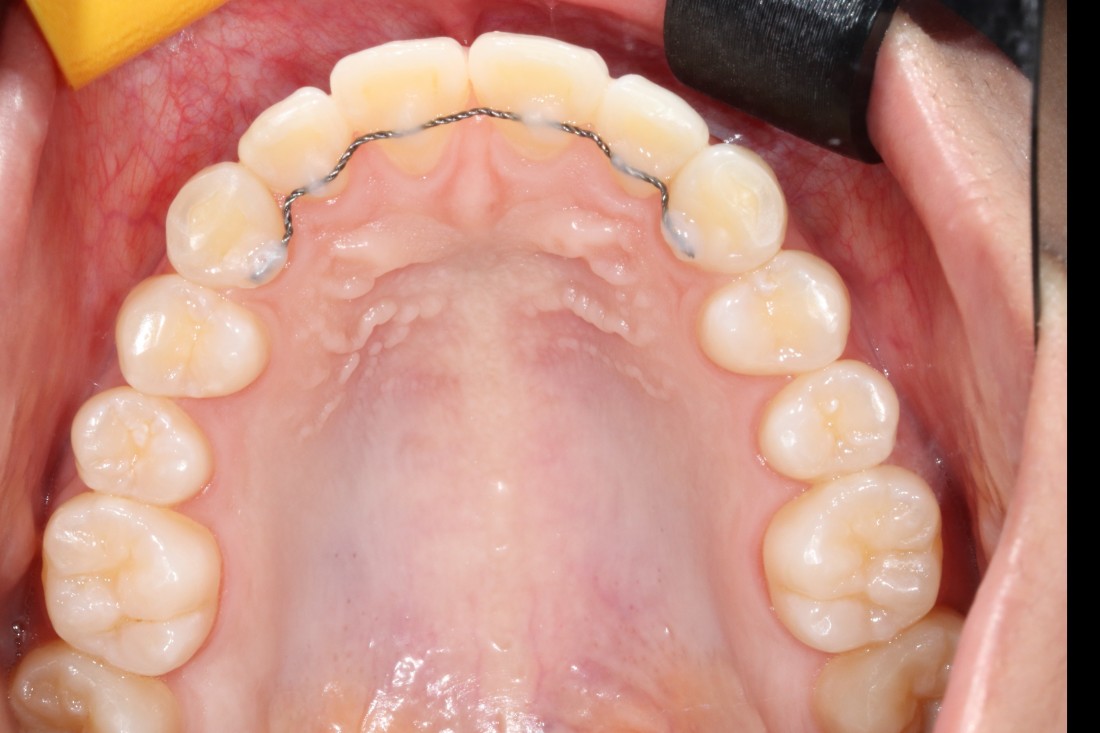

광주 교정치과

충치치료 + 치아교정 동시 케이스

광주 교정치과 추천하는 이유는

전문의 충치치료까지 동시에 가능하여

토탈 구강건강 관리를 받으실 수 있기 때문입니다.

5층은 일반진료센터,

4층은 VIP 치아교정실로 운영되어

치아교정 진료만을 담당하는

교정전담 의료진의 세심한 케어로

광주 교정치과를 추천합니다.